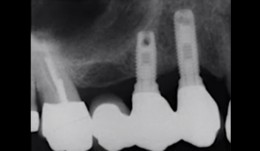

Implant planning

Prof. Homa ZadehIn 3 lessons, Professor Zadeh discusses planning and distribution of implants in both partially and fully edentulous patients. The main learning objective is to understand what considerations affect clinical decisions to produce best aesthetic outcomes in such patients.